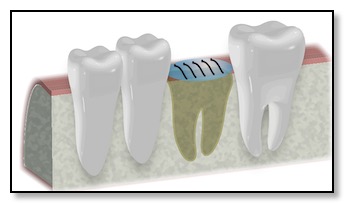

Jawbone Preparation through Bone Grafting (if necessary)

While extracting the tooth, Dr. Tsai will also clean the socket and prepare it for bone grafting and the application of a membrane. This step is crucial for the healing process, especially if you're considering a dental implant, particularly an all-ceramic one. The healthy blood present in the socket will flow into the bone grafting chips and serve as a framework, blending with the bone grafting material.

As a result, the fluid thickens and helps facilitate healing around the bone grafting structure. Over the next four to five months, your body will gradually absorb the bone graft chips, replacing them with your own natural bone. This integration process typically takes around four to five months to complete.